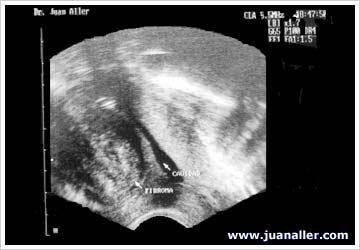

WAB 9-1: SONOHISTEROGRAFÍA - MIOMAS

Fibroma Vs. Pólipo

Fibroma

Fibroma tipo I

Fibroma Subseroso SHG